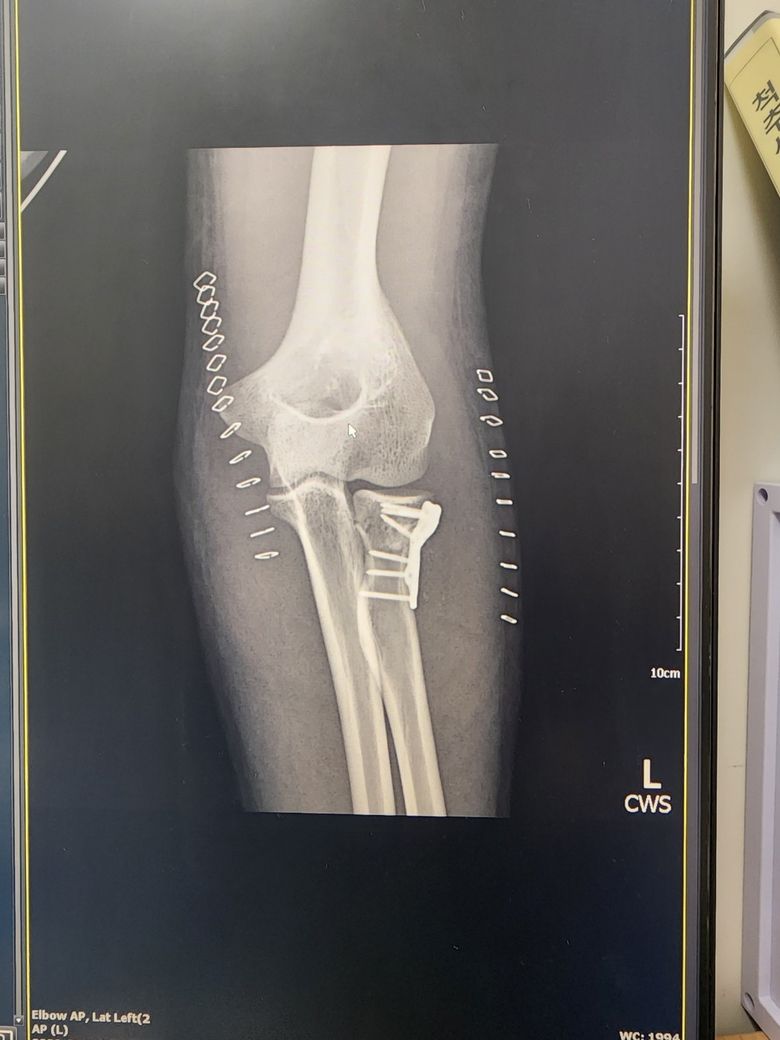

요골두 골절 수술 후 팔꿈치에 뼛조각같은게 만져지는데 괜찮을까요?

5월 21일 자전거를 타다가 벽에 부딫혀서

요골두 골절, 내/외측측부인대 파열, 삼두근 근육 및 힘줄 손상 진단을 받아서

관혈적 정복술 및 금속 내고정술, 인대 봉합술, 힘줄 봉합술을 받았습니다.

이때까지는 몰랐는데, 진료 받고 나서 팔꿈치 바깥 끝부분쪽에 뼛조각같은게 만져집니다.

수술 전 엑스레이 및 mri 촬영하고 삼두근육 힘줄이 뼛조각을 하나 물고 떨어졌다는데, 이것인가 싶기도 하고

심한 외상후 석회질이나 골화가 생길수 있다는데 이게 회복에 영향을 주거나 관절 가동범위에 제한이 되는지, 나중에 제거해야하는지 궁금합니다.

우선 현재 엑스레이상 의심이 되는 부분은 관찰이 되지 않습니다.

뼈조각이나 골화의 경우 추후 관절운동범위의 제한이 올수도 있기에 우선 증상지속시는 정형외과에 내원하시어 CT등으로 정확한 진단을 받아보시는 것을 추천드립니다.